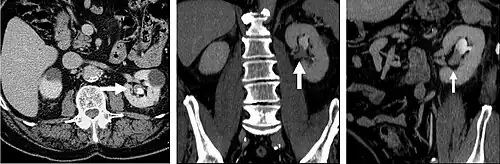

Delayed phase

Delayed phase imaging (figure 5) encompasses scanning at a variety of different times following contrast administration, and depends on the pathology in question. Typical delayed imaging times range from a few minutes to up to 15 minutes or longer. The most common indications for delayed phase imaging are evaluation of the kidneys, collecting system (ureters and bladder) and specific kidney, liver, and adrenal tumors. Evaluation of the kidneys, ureters and bladder are discussed separately in the renal imaging section. Cholangiocarcinoma occurring within the extrahepatic biliary tree or intrahepatic cholangiocarcinomas are a common reason for delayed imaging. Cholangiocarcinomas are fibrotic tumors which enhance slowly, and are usually imaged following a 10-15 minute delay. Similarly, adrenal masses can be evaluated with multiphase imaging including an unenhanced CT, portal venous phase and a 10 minute delay CT which allows for evaluation and calculation of the enhancement and washout characteristics aiding in distinguishing benign adrenal adenomas from other adrenal masses.

Outside of the evaluation of masses, delayed phase images can be used in the evaluation of active vascular extravasation in trauma patients, vascular malformations, and aneurysm disruption.